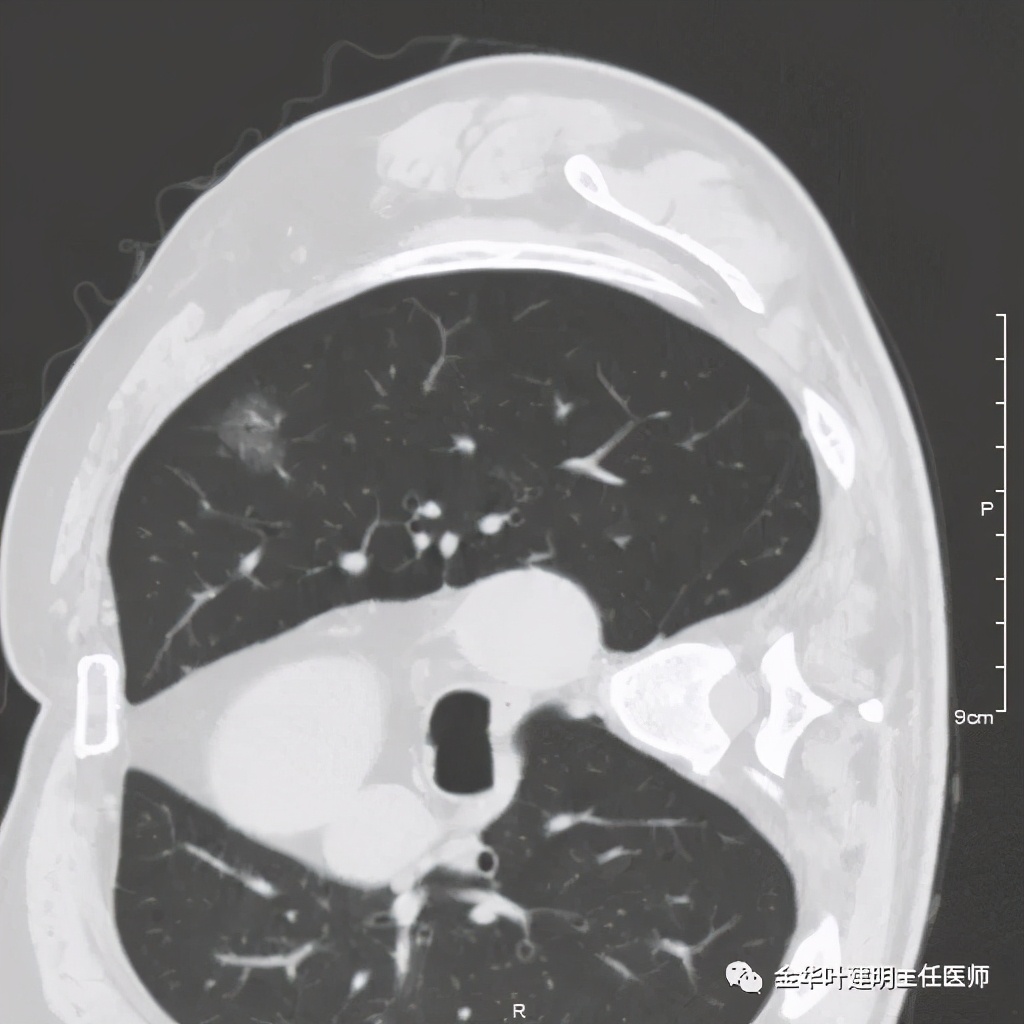

五、浸润性腺癌之粘液腺癌:

影像特征:这个病例是我在术前仅凭影像就判断其为粘液腺癌,术后确诊的。粘液腺癌表现为 实性乏收缩力、密度较均匀 的实性结节。病灶的边界一般非常清楚,没有毛刺、磨玻璃、卫星灶等,但又乏收缩力,像本例紧贴胸膜也不会有牵拉凹陷;同时病灶的密度又比较均匀(粘液成份)。良性肿瘤密度要更高些、慢性炎没有这么光整的边界,也容易有瘢痕收缩方面的影像表现、其他实性的腺癌则要有收缩力、腺泡型虽然也缺乏收缩力,但密度要不均匀些。